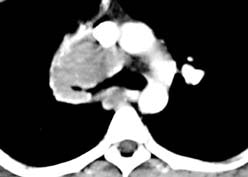

Example: The images below illustrate a case of non-small cell lung cancer which involved the carina (see drawing at right). Although this is typically considered a non-resectable T4 lesion, the tumor was treated surgically with a right carinal pneumonectomy due to the patient's young age. (Case courtsey of Dr. Douglas E. Wood, M.D.).